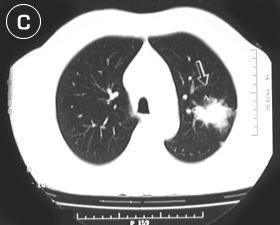

• Corte Tomográfico "C"

a nivel supracarinal:

• Flecha Blanca/negra: Tercio inferior de la lesión tumoral, sólida mal definida en sus bordes y se define en su ubicación segmentaria.